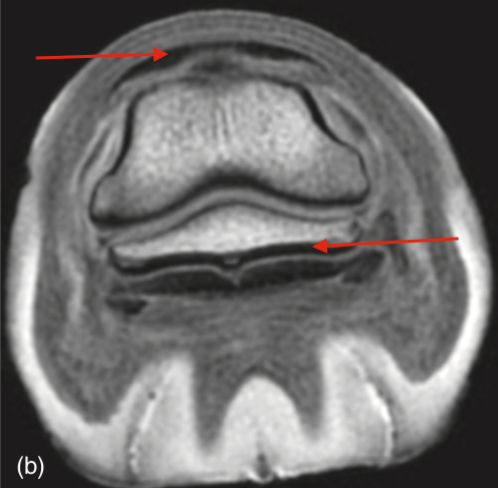

(Note hypointense fluid in DIP and NB - red arrows)

Appearance of fat and fluid on T2-weighted images

On T2 - 2 things are white; fat and water

Trabecular bone and synovial fluid are both hyperintense. The easiest way to distinguish T1 and T2 images is to observe the signal intensity of fluid.